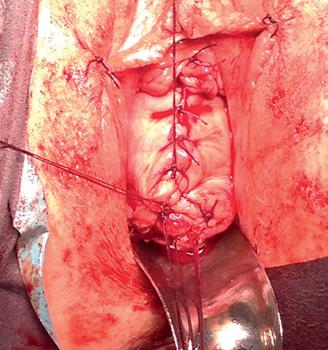

Imagine 1. Prolaps de boltă vaginală

Se efectuează RMN abdomino-pelvin nativ și cu CIV ce arată acumulare neomogenă cu aspect fibrotic inflamator situată presacrat (anterior de spațiul intervertebral L5-S1 paramedian drept) ce interesează în marginea ei și ureterul drept pe o lungime de cca 3 cm, prezintă modificări aderențiale față de ovarul drept și o comunicare cu o colecție situată posterior de ligamentul prevertebral la nivelul spațiului discal L5-S1, spondilodiscită L5-S1, uter cu dimensiuni mult reduse, ovare si trompe uterine prezente.

Imagine 4. IRM pelvin

În urma corelării elementelor clinco-imagistice se stabilește diagnosticul actual de prolaps boltă vaginală recidivat, stenoză ureterală dreaptă protezată cu stent pentru UHN gr. II-III, sacrodiscită, malformație complexă utero-cervico-vaginală U5bC4V4 (Sindrom MRKH).

Se intervine chirurgical și se practică ureteroliză dreaptă, excizia meșei de polipropilena pe cale abdominală (pentru rezolvarea focarului infecțios și consecințe-

lor sale) și colposuspensia la ligamentele sacrospinoase pe cale vaginală, pentru rezolvarea prolapsului genital.

Imaginile 5 și 6: Aspect intraoperator